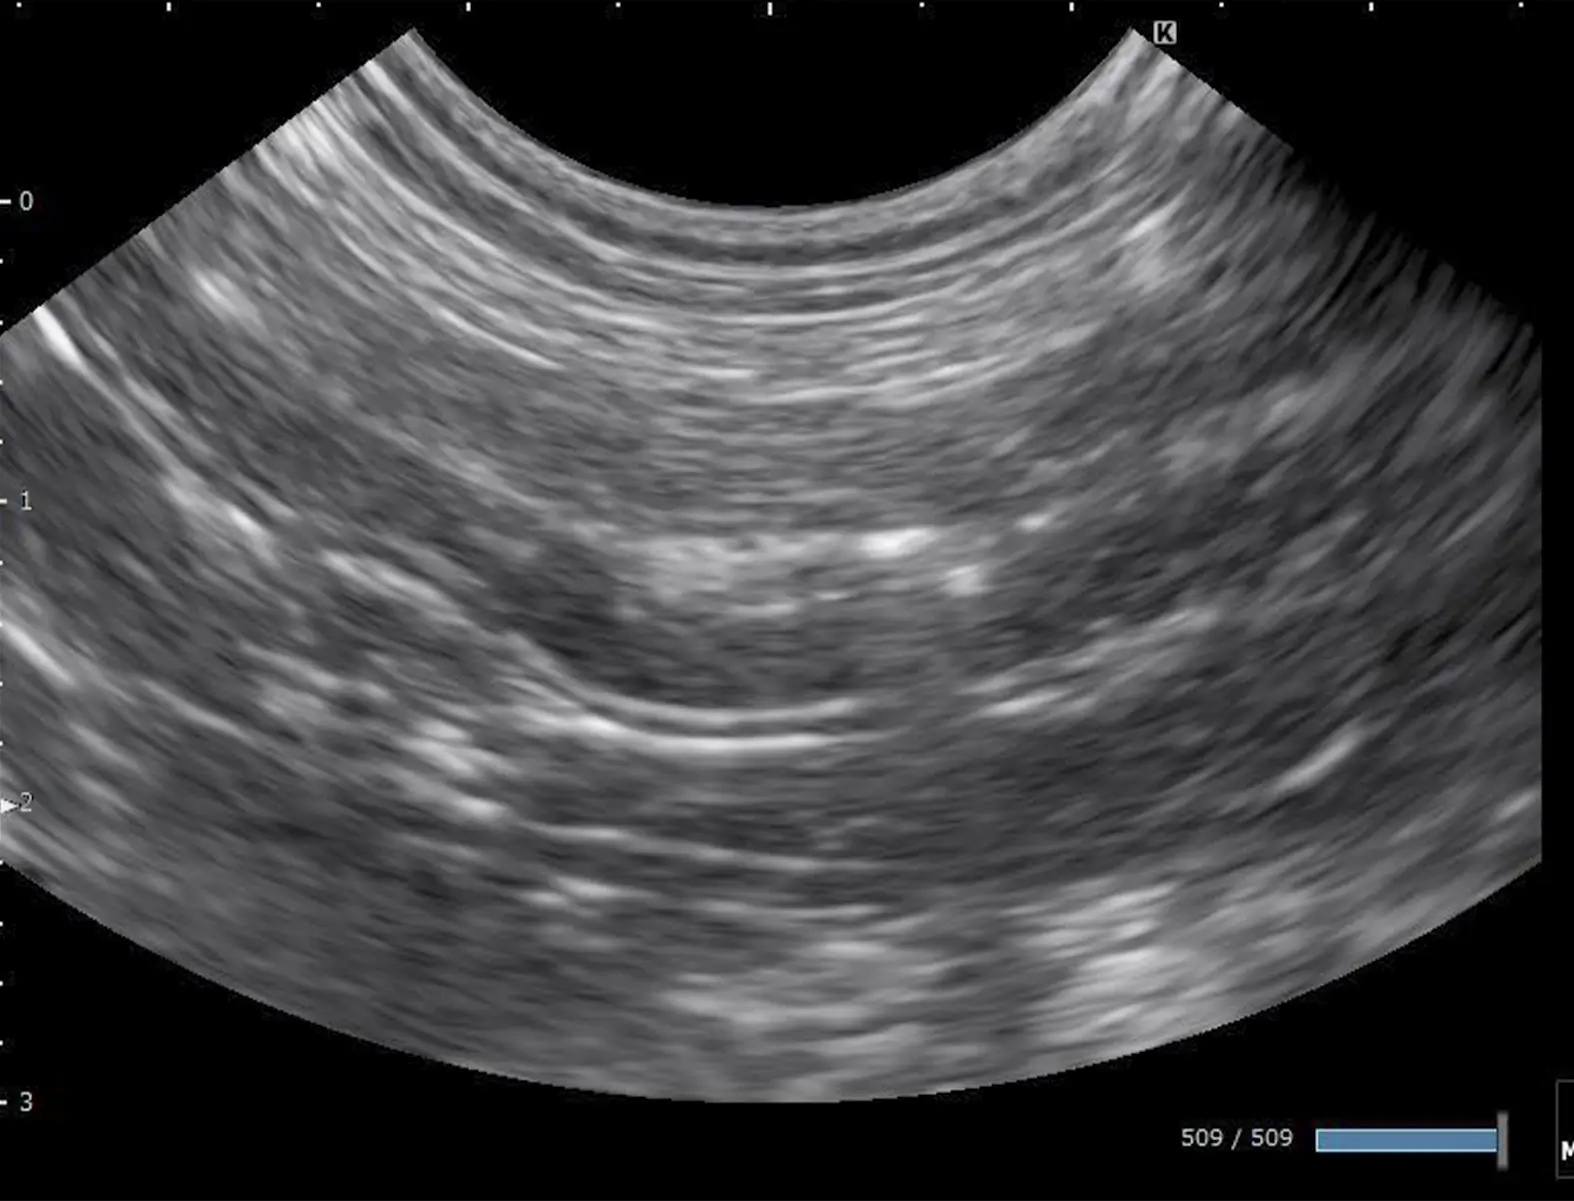

画像検査

X線検査では腹部臓器の大きさや形、位置の変化などを評価します。超音波検査では無麻酔で腹部臓器の詳細な評価が可能です。

病理検査

超音波検査下で採取した細胞や内視鏡検査や開腹手術で採取した組織から確定診断を行います。